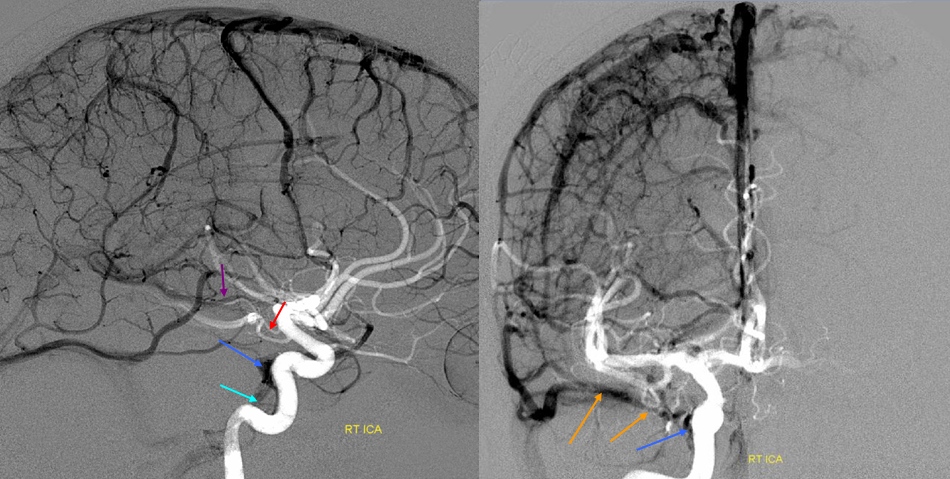

Sagittal Sinus Thrombosis — collaterals.

All of the above anatomic knowledge can become very useful in evaluation of venous thrombosis. Numerous collateral pathways develop in this setting attempting to compensate for the loss. The most dramatic cases usually involve the largest channel — the superior sagittal sinus. In this case, a man presented with what initially was thought to be vasculitis-related brain hemorrhage. Subsequent workup led to an angiogram, where sagittal sinus thrombosis with extensive trans-cerebral and trans-osseous emissary vein collateral channels was seen. In retrospect, these findings were present on the patient’s earlier contrast MRI. “Venovibe” or other contrast-enhanced MR venograms can very sensitive, particularly when interpreted with the appropriate index of suspicion. Noncontrast 2-D time of flight MRV I consider to be next to useless as a problem-solving technique. Any thin-slice postcontrast T1 study is vastly superior.